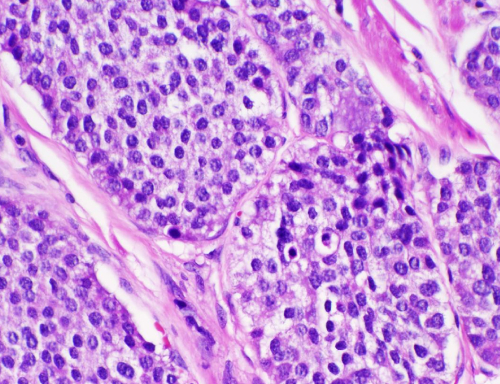

Histopathology refers to the microscopic examination of tissue in order to study the manifestations of disease. Specifically, in clinical medicine, histopathology refers to the examination of a biopsy or surgical specimen by a pathologist, after the specimen has been processed and histological sections have been placed onto glass slides.